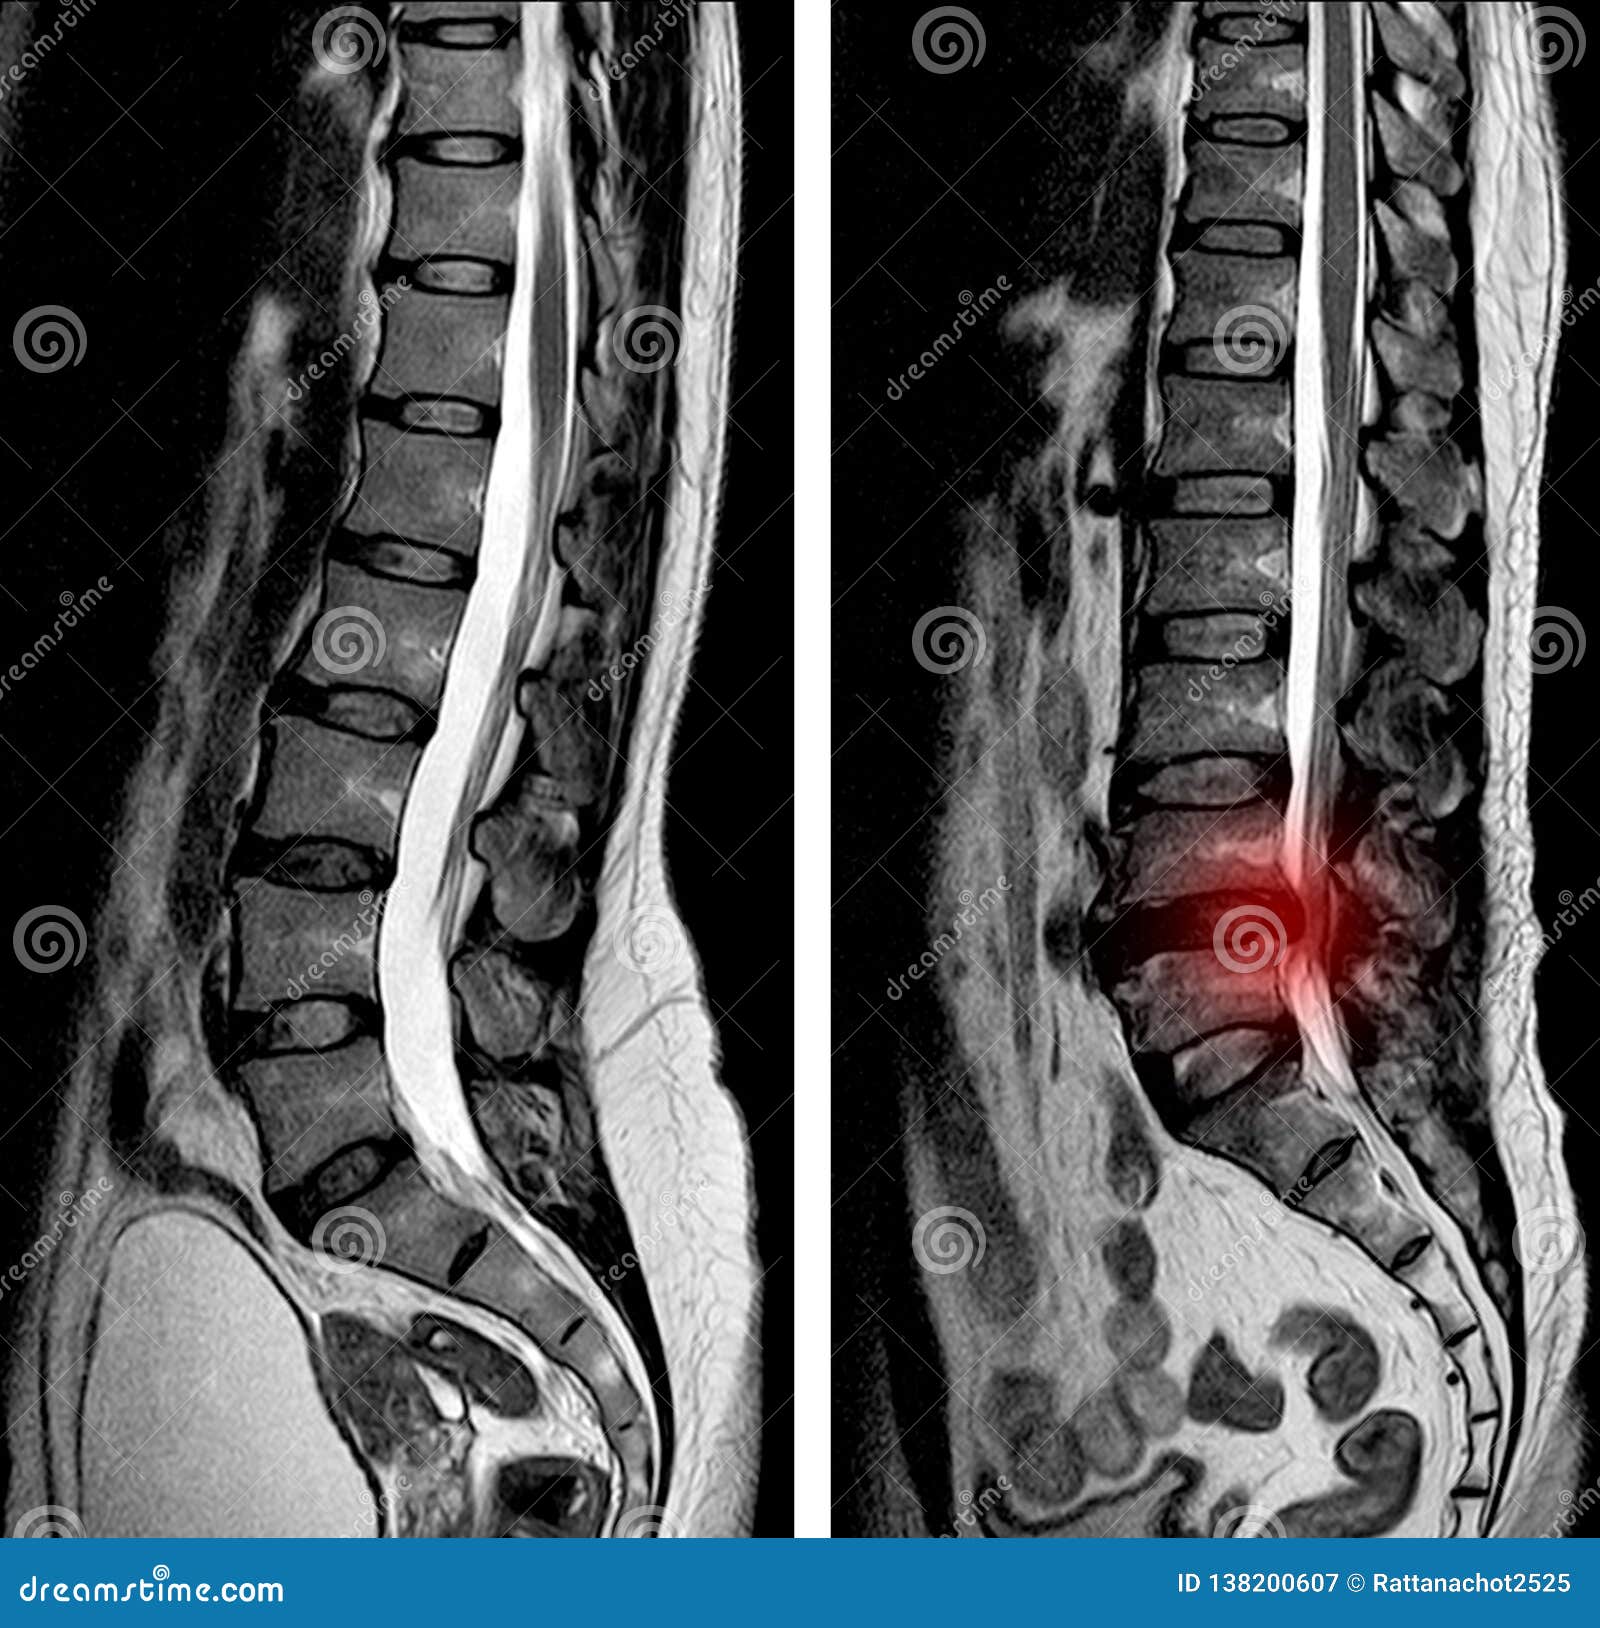

Mri Of Lumbar Spine Stenosis Stock Photography | CartoonDealer.com …

Mri of Lumbar Spine Stenosis Stock Image – Image of neurosurgery …

MRI lumbosacral spine of the patient showing mild to moderate lumbar …